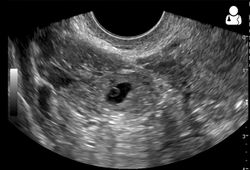

An ultrasound showing a gestational sac with fetal heart in the fallopian tube has a very high specificity of ectopic pregnancy. It involves a long, thin transducer, covered with the conducting gel and a plastic/latex sheath and inserted into the vagina.[32] Transvaginal ultrasonography has a sensitivity of at least 90% for ectopic pregnancy.[5] The diagnostic ultrasonographic finding in ectopic pregnancy is an adnexal mass that moves separately from the ovary. In around 60% of cases, it is an inhomogeneous or a noncystic adnexal mass sometimes known as the "blob sign". It is generally spherical, but a more tubular appearance may be seen in case of hematosalpinx. This sign has been estimated to have a sensitivity of 84% and specificity of 99% in diagnosing ectopic pregnancy.[5] In the study estimating these values, the blob sign had a positive predictive value of 96% and a negative predictive value of 95%.[5] The visualization of an empty extrauterine gestational sac is sometimes known as the "bagel sign", and is present in around 20% of cases.[5] In another 20% of cases, there is visualization of a gestational sac containing a yolk sac or an embryo.[5] Ectopic pregnancies where there is visualization of cardiac activity are sometimes termed "viable ectopic".[5]

Transvaginal ultrasonography of an ectopic pregnancy, showing the field of view in the following image

A "blob sign", which consists of the ectopic pregnancy. The ovary is distinguished from it by having follicles, whereof one is visible in the field. This patient had an intrauterine device (IUD) with progestogen, whose cross-section is visible in the field, leaving an ultrasound shadow distally to it.

Ultrasound image showing an ectopic pregnancy where a gestational sac and fetus has been formed